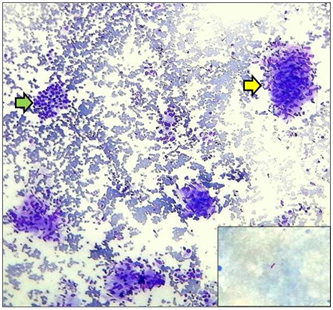

A 7-year-old female presented with a midline neck swelling since last 2 months associated with fever and fatigue. There was no history of anorexia or weight loss, dysphagia, respiratory or genitourinary symptoms, nervousness, tachycardia and palpitation. Her past, medical as well as family history was non-contributory. On physical examination, she had a body height of 128 cm and a body weight of 30 Kg and a basal metabolic rate of 18.3 kg/m2. Her vitals were within the normal limits and no pallor, icterus or any lymphadenopathy was evident. On local examination, there was a multinodular swelling in the thyroid gland region which was more prominent on the right side than the left and measured 4cm x 3cm in size. The swelling moved up with deglutition. It was soft to firm in consistency and non-tender. The overlying skin was unremarkable Figure 1. No abnormality was detected on her systemic examination. The laboratory investigations revealed a haemoglobin level of 13.4 g/dl, total leukocyte count of 5300/mm3 with differential being of 52% lymphocytes and a platelet count of 510,000/µl. The erythrocyte sedimentation rate (ESR) was 48 mm/ first hour and the urine as well as blood cultures were negative. Renal as well as liver function tests were normal. T3, T4 and thyroid stimulating hormone were within the normal limits. Serum tests for antibodies to anti-thyroid peroxidase, human immunodeficiency virus, hepatitis B surface antigen and syphilis were negative. X-ray chest was normal. Ultrasonography (USG) of the thyroid gland region showed a diffusely enlarged thyroid gland with altered echotexture. Multiple ill-defined and few well-defined nodules were seen in both lobes. Largest nodule in right lobe measured 15mm x 11mm and that in the left lobe measured 10mm x 6mm. No cervical lymphadenopathy was seen. Based on these clinical, laboratory and radiological findings, a provisional diagnosis of multinodular goitre was made. To arrive at a conclusive diagnosis, Fine Needle Aspiration Cytology (FNAC) was performed. Two passes at two different sites of the lesion were done. Thick cheesy material was aspirated in both the attempts. This material was pushed onto the clean glass slides and the smears were drawn. The smears prepared, were stained with May-Grunwald Giemsa (MGG) stain followed by microscopic examination. FNAC smears revealed numerous epithelioid cell granulomas with peripheral lymphocytic cuffing, langhans giant cells and caseating necrosis. Scattered clusters of benign thyroid follicular epithelial cells were also seen in the background Figure 2. Special stain for tubercle bacilli (Ziehl-Neelsen stain) showed few acid-fast bacilli (AFB) Figure 2-Inset. Based on these cytological features, a final diagnosis of thyroid gland TB was established. She was investigated further to look for possible sites harbouring the tubercular infection. However, no AFB was found in her sputum as well as urine samples. Mantoux test resulted in 10 mm induration. On abdominal USG, no lymph node enlargement was seen. The patient was put on standard short course antitubercular treatment (ATT), to which she responded well as there was a gradual regression in the thyroid gland size in subsequent follow-ups.

Figure 2 Epithelioid cell granuloma (yellow arrow) and benign thyroid follicular epithelial cells (green arrow) (MGG, x100). [Inset: Ziehl-Neelsen stain showing presence of AFB].